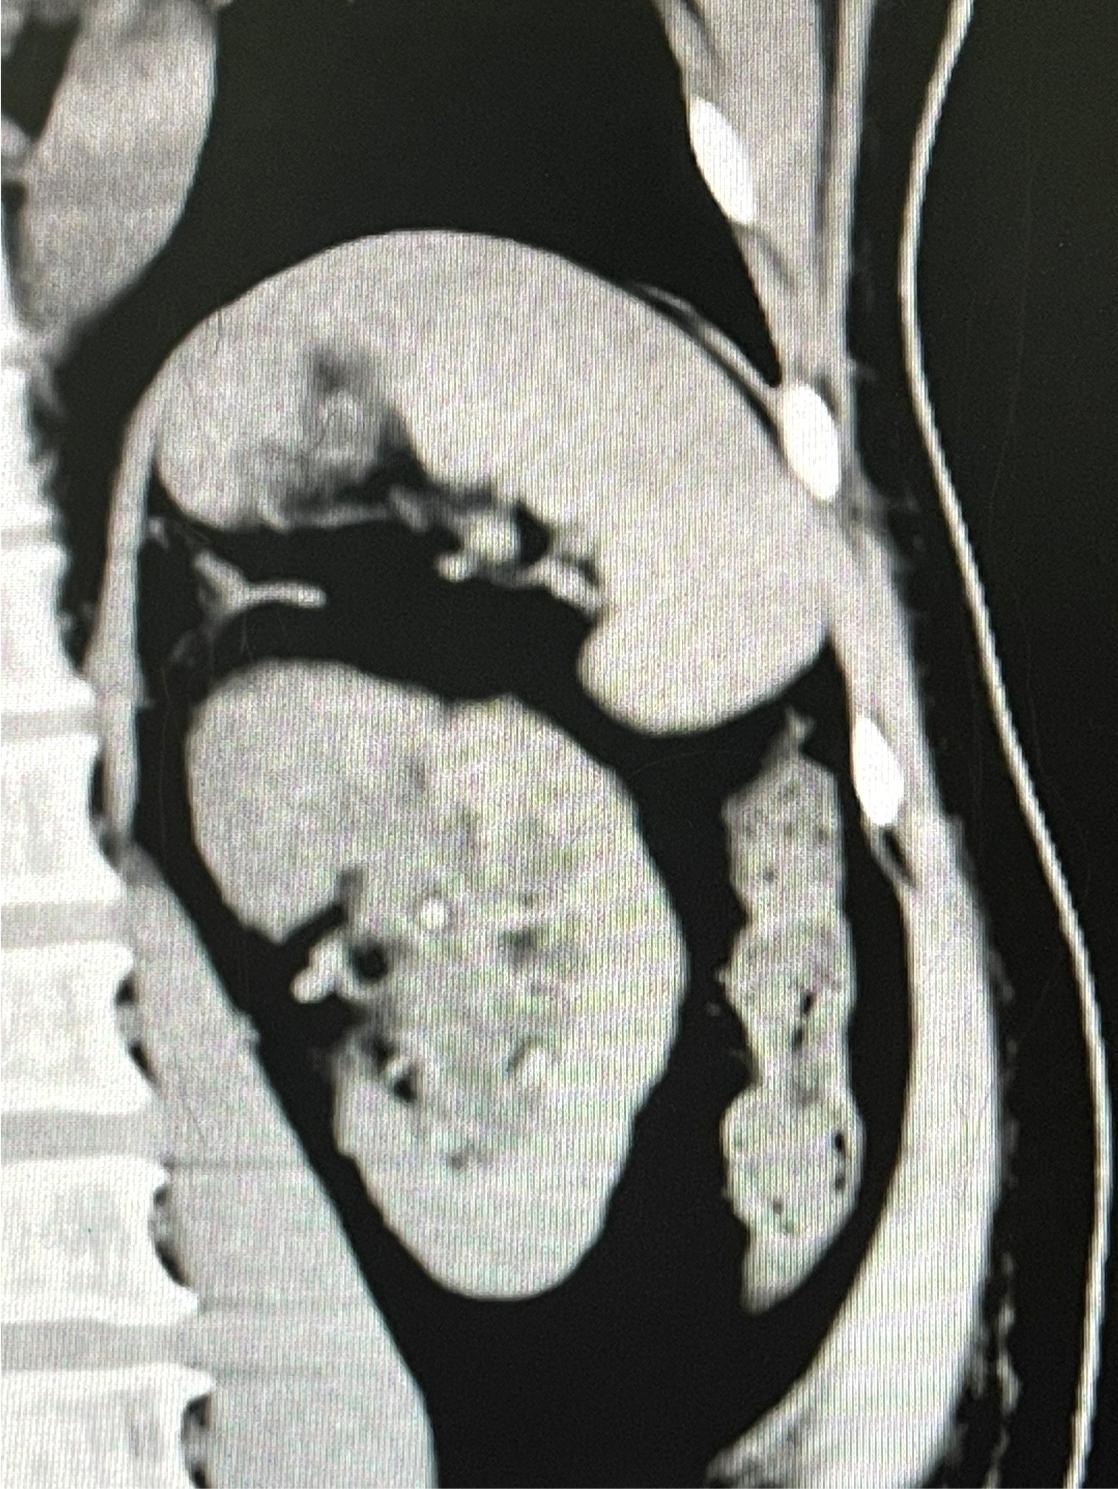

钦州宝顺医院副主任医师、泌尿外科专家、钦州宝顺医院副院长王宗绫 结石、前列腺、肿瘤一直是困扰男性泌尿系统健康的三大顽疾。作为医学技术人员,王宗绫以强烈的事业心和高度的责任感,视事业如生命,把破解泌尿外科难题当作一生的追求。自大学毕业从医20余年以来,日复一日,年复一年,他一直专注于泌尿外科的研究,不断努力提高自己的医术诊治水平,始终用真诚与爱心做一名病人满意、群众欢迎的好医生。 王宗绫认为,医生的职责就是为病人治好病和服务好病人。想要做一名好医生,为病人减轻痛苦、获得病人的认可,必须要有过硬的技术本领。为了充实和提高自己的专业理论水平和临床诊治能力,王宗绫始终将攻克泌尿外科难题与为群众提供精湛技术服务紧密结合起来,以解决复杂疑难泌尿系统疾病为己任。他远赴南方医科大学和广州医科大学进修1年,师从中国著名泌尿外科刘春晓和李逊教授学习先进的泌尿外科诊治技术以及尿路结石微创手术。平时不管工作再忙,他都要挤出时间学习专研专业理论或者了解国内外最新、最前沿的诊治技术发展情况。每遇到疑难病例、复杂手术,他常常要仔细查阅相关资料,反复推敲。

医心向党,初心如磐。王宗绫二十余年的心血都用在微创和超微创手术破解泌尿顽疾。他只是民营医院普通医生,给患治好病就是最高荣誉。(通讯员:黄孟林) |